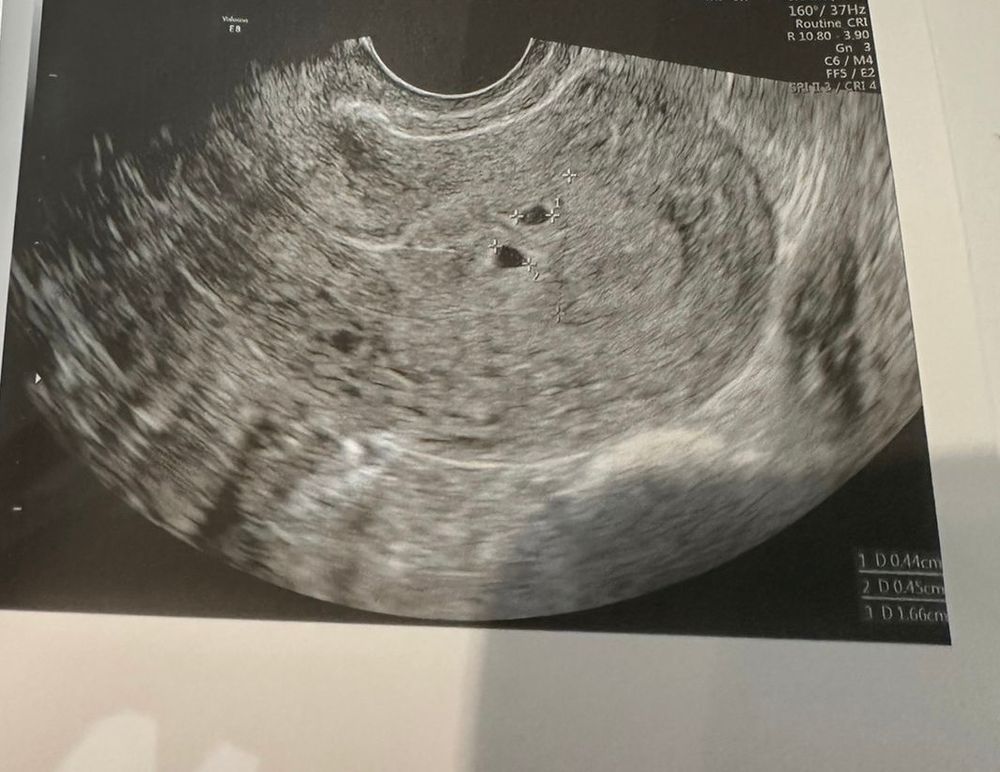

Многоплодная беременностьВсем привет! с 13.08 по 16.08 были месячные, 21.08 и 26.08 половые контакты. На второй день задержки 10.09 (месячные должны были начаться с 09.09) сделала тест и он показал две полоски, на следующий день сразу сходила на узи, там показало 2 округлых включения, хгч на тот день был 528.5, через 3 дня сдала еще один анализ он показал 1609. Девочки, это двойня? 🥺

Вот фото двойни на самом первом узи. На хгч не ориентируйтесь. Ваши похожи, но раз поставили под вопросом, значит нужно чуть подождать.

yamama, плюс 1.8 мм очень маленькие. У меня они были по 4,5 мм, но там и хгч был около 3х тыс